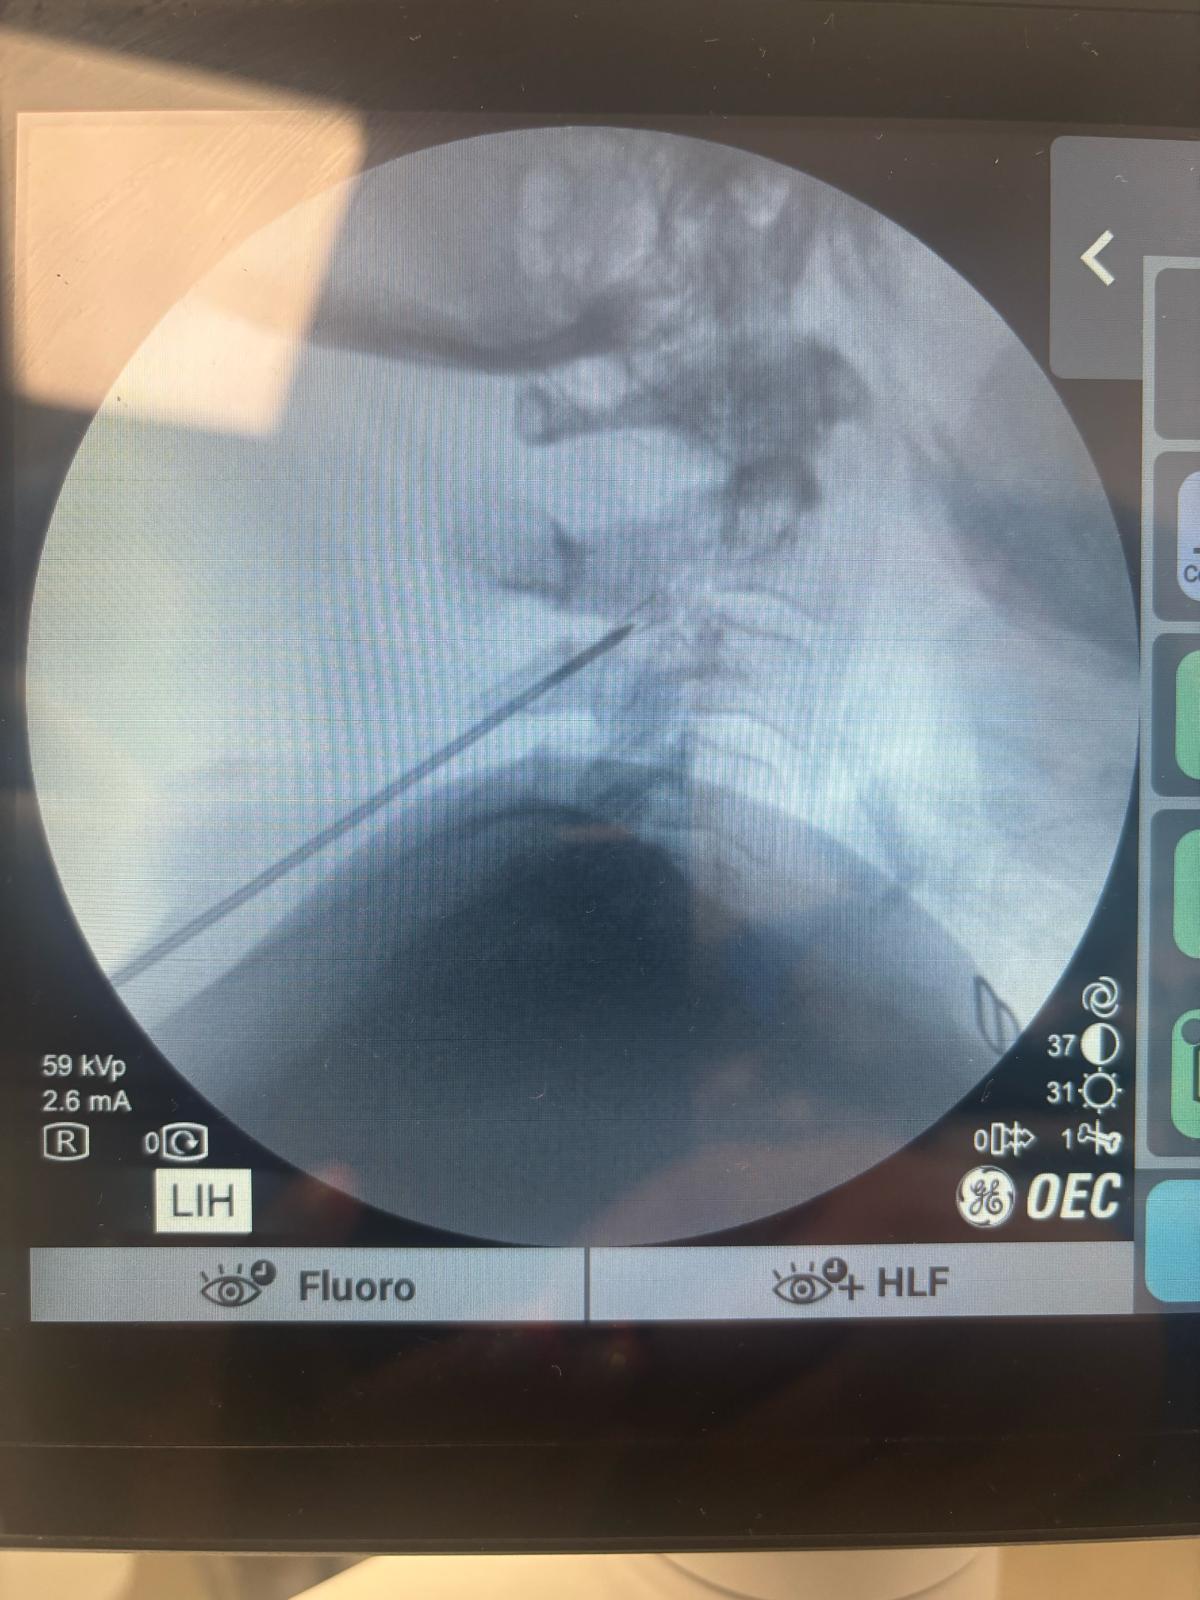

Image-Guided Precision: Using fluoroscopy (X-ray guidance), your doctor places a specialized needle near the third occipital nerve.